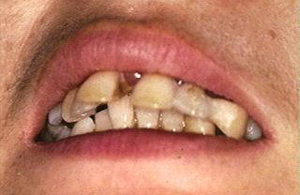

その結果、1本の歯が傾きますと両隣の歯だけでなく対合歯にも影響が波及し歯並びの乱れが目立つようになります(Photo-1)また前歯では反っ歯になり口を閉じて歯が見えるようになります(Photo-2)

また、(Photo-5.1)ならびに(Photo-5.2)の症例はいずれも末期の歯周病で歯の動揺も大きく、さらに排膿や腫れが見られ抜歯が必要でした。しかし、同様の処置を行ない仮固定の交換のみで初診時の症状は解消し、すでに7年間経過しています。抜歯に該当する歯であっても仮固定で支え、FDC治療システムと熱心なホームケアによって歯を残すことが可能です。

ノウハウもなく単に歯を連結し病原菌除菌も行なわなければ「砂上の楼閣」にすぎません。このような装置は早ければ半年から数年で大きな動揺がみられ腫れや咀嚼困難が生じます。結局、連結歯すべて抜歯することが多いようです「Photo-1」